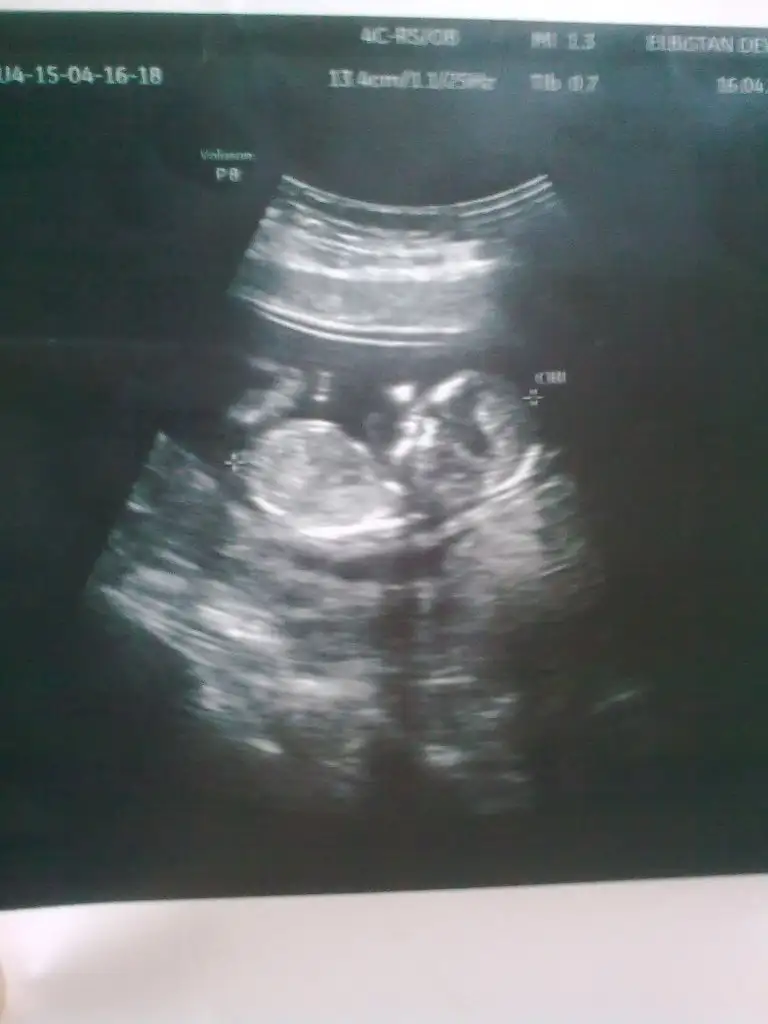

Kız zannedersemKizlar banada yorum yapin nolurrr catliyorum merakdannnnn

Canim ben kiz dedim seninkine...bence kiz diyorum...nub u paralel cunku...bariz kendin de gormussun...hayirlisi olsun canimBaksana ben mı yanlıs bakıyorum canm

Canim ben kiz dedim seninkine...bence kiz diyorum...nub u paralel cunku...bariz kendin de gormussun...hayirlisi olsun canim

Buyuj ihtimak kizz...kızlar 14 haftalık hamileyim dr.bişey demedi cinsiyetine lütfen yorumlarmısınız....merakla bekliyoruz......